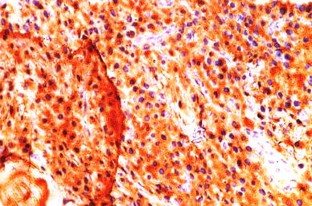

Primary localized amyloidosis in the head and neck region is a rare entity. The most commonly involved organ is larynx. Primary amyloidosis localized to the sinonasal tract is extremely rare. We report one such case along with a brief review of the associated literature. The aim of reporting this case is to emphasize the fact that sometimes nasal amyloidosis can also present with signs and symptoms of nasal and nasopharyngeal malignancy. The definitive diagnosis in such cases depends upon histopathology and further confirmed by immunohistochemistry. A 55-year old male presented with recurrent episodes of nasal bleed, bilateral nasal obstruction, and bilateral hearing loss from last 7 years. On clinical examination a mass was found in the nasal cavity on both sides reaching up to the nasopharynx. Contrast enhanced CT scan revealed that the mass was extending up to the skull base and destroying bony landmarks of the nasal cavity and paranasal sinuses. Mass was proved to be amyloidosis after histopathological examination. It showed multiple blotches of globular submucosal deposit of amyloid, on staining with Congo red. Immunohistochemistry confirmed AL amyloidosis with expression of mixed kappa and lambda light chain immunoglobulin (κ > λ). No evidence of systemic amyloidosis was found after proper work up. It was managed by conservative surgery.